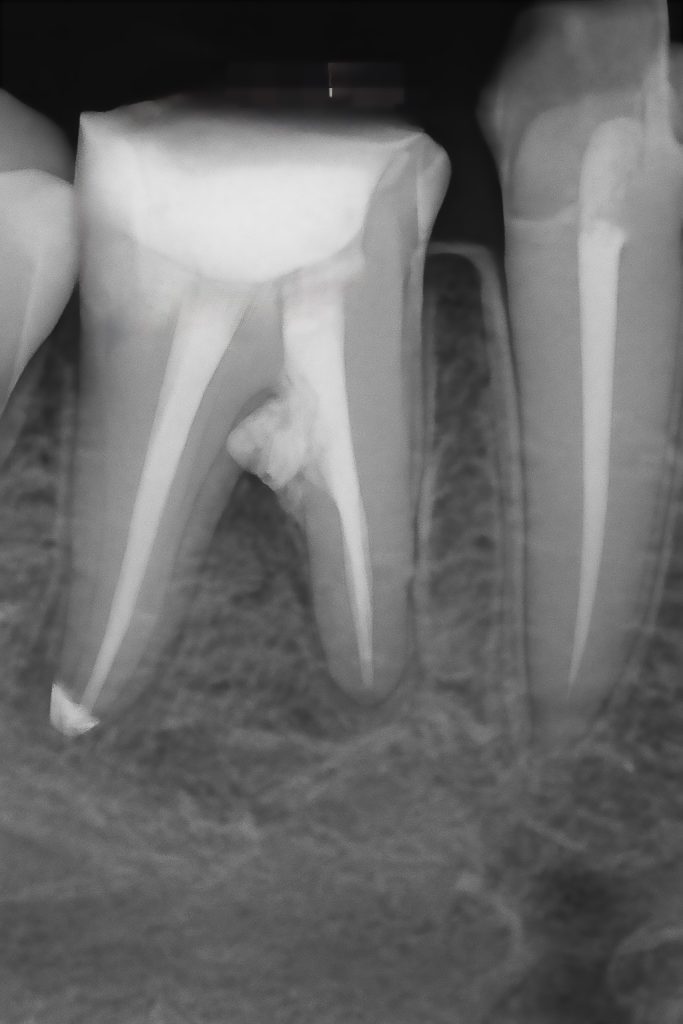

A mechanical ledge was identified in the mesial canal during negotiation. Glide path re-established with #08–10 K-files using watch-winding motion and chelating lubricant (RC-Prep). A small strip perforation was observed and sealed with ProRoot MTA (Fig 3).

- Fig 3: Bypassed ledge and MTA placed in perforation area.